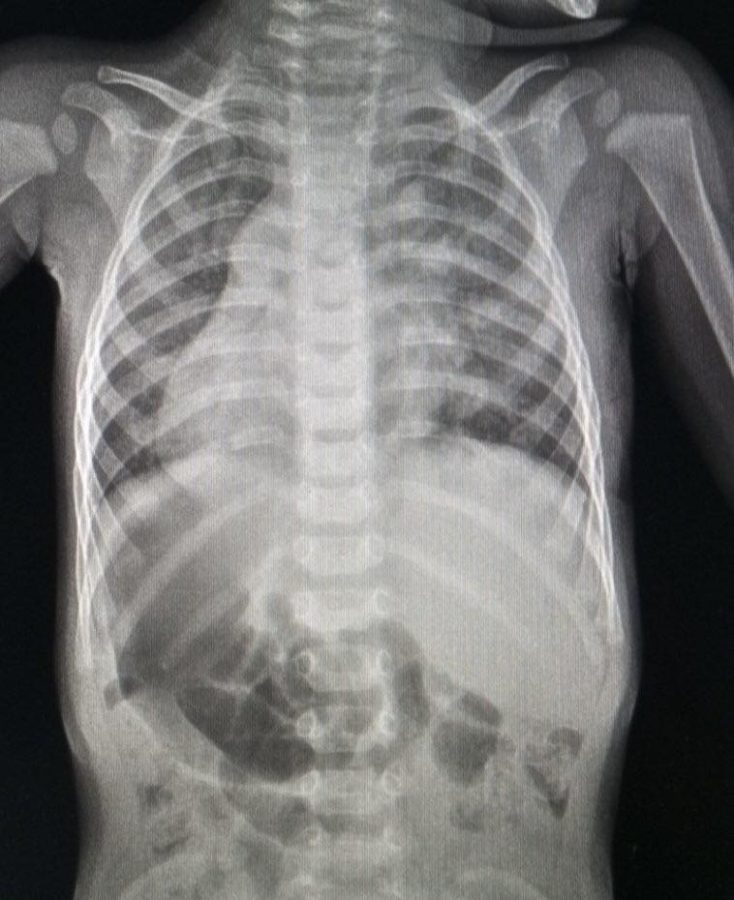

Серце, селезінка та підшлункова залоза малюка знаходяться справа, а печінка з апендиксом – зліва. Сама по собі така анатомія хоч і є вкрай рідкісною, проте вважається варіантом норми.

Але у дев’ять місяців під час планового огляду педіатр почув шуми в серці дитини. Медики виявили складну вроджену ваду – дефект міжпередсердної перегородки з частковим аномальним дренажем легеневих вен.

Через анатомічні особливості судини впадали не у своє рідне ліве передсердя, а у праве, яке фізично розташовувалося зліва. За порятунком родина звернулася до львівських фахівців.